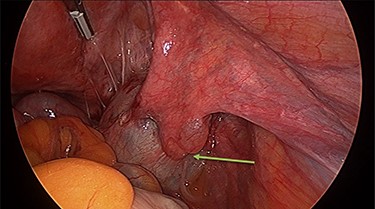

Operation findings consisted of left hydrosalpinx and para-tubal cyst adhered to pouch of douglas, with the left tube torted 3 times (Figs 4 and 5). There was a 5-cm para-tubal cyst on the right tube adhered to right side of pelvis/rectum/pouch of douglas (Fig. 6). The ovaries appeared normal.